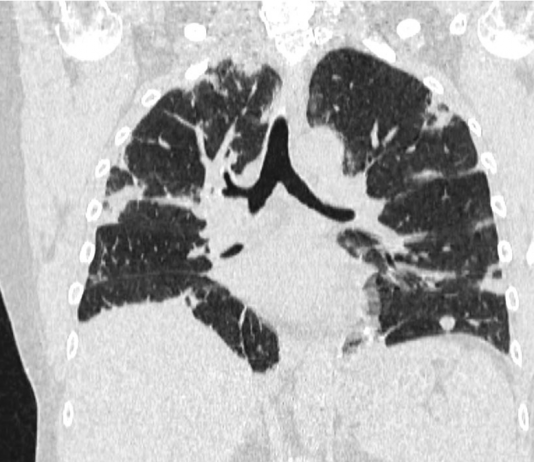

Maschio, 51 anni. Anamnesi patologica remota muta. Il paziente è residente a Fabrizia,...

Maschio, 51 anni. Anamnesi patologica...